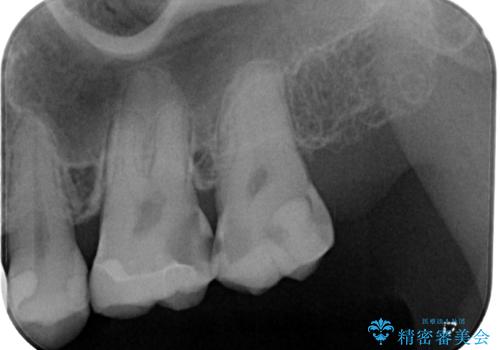

既に根管治療を終えている状態での来院で、クラウンを装着を希望されていらっしゃいました。

レントゲン写真より根管治療のやり直しをお勧めしたところ、ラバーダム使用下で処置を行うことを希望されたため、根管治療を行った後にオールセラミッククラウンにて補綴治療を行うこととしました。

後方は歯肉内にまで虫歯が及んでいたため、歯肉の一部を切除して、クラウンとの境目を明示して処置を行いました。